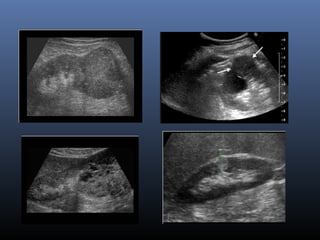

MSCT

 Sang th ng d ng nang d ch, v i đđ UHươ ạ ị ớ

=10

 V trí: v th n, c nh b th nị ỏ ậ ạ ể ậ

 Th ng có c hai bên th nườ ở ả ậ

 Nang cũ : đóng vôi vách

 Khi nang bi n ch ng : thành ph n d ch trongế ứ ầ ị

nang không thu n nh tầ ấ

 Nang xu t huy t : d ch tăng đ m đ (60 UH)ấ ế ị ậ ộ

 B t thu c c n quang nh váchắ ố ả ẹ ở

 Phân tích hình nh c a các vách: d y, m ng,ả ủ ầ ỏ

m t/nhi uộ ề

 Các n t vách +/-ố ở

Siêu âm

 T n th ng tròn , echo tr ng đ ng nh t, vổ ươ ố ồ ấ ỏ

r t m ngấ ỏ

 V trí: v , c nh bê th nị ỏ ạ ậ

 Nhi m trùng, xu t huy t=> d ch bên trong sễ ấ ế ị ẽ

không còn đ ng nh t và tăng nhồ ấ ẹ

 Chuy n ác tính : vách d y, n t ++, vôi +ể ầ ố

 => phân lo i Bosniakạ